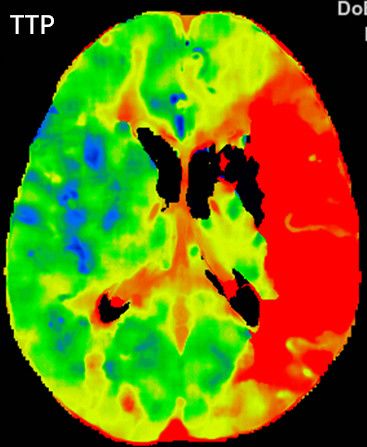

多模式CT影像提示:左侧大脑中动脉M1段闭塞,存在CBF-CBV不匹配。

图2 CTA显示左侧大脑中动脉M1段闭塞

图3 CTP存在CBF-CBV不匹配

1.术前诊断:急性脑梗死,左侧大脑中动脉闭塞。

2.手术指征:患者应用阿替普酶溶栓后症状仍持续加重,CTA示左侧大脑中动脉闭塞。CTP存在CBF-CBV不匹配,有介入治疗指征。